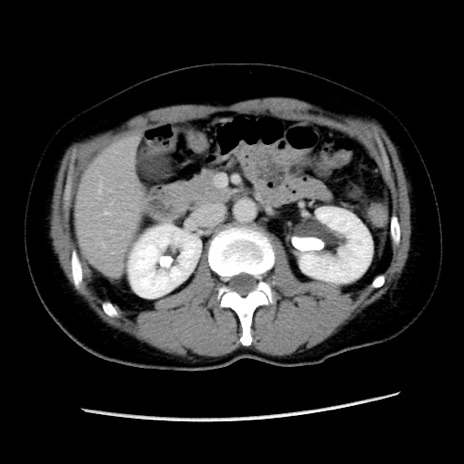

症例10(横断像)

【症例】 50歳代女性

【主訴】 腹痛

【現病歴】前日生レバーを食べた。今朝に排便あり。 昼前に突然発症の腹痛を生じ、当院救急外来を受診した。

【身体所見】 意識清明、腹部:平坦、軟、下腹部やや左を中心に圧痛・反跳痛あり、筋性防御あり

【データ】WBC 7800、CRP 0.07